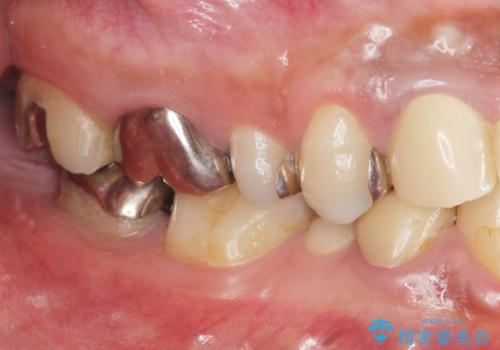

- 長年虫歯の治療を受け続けたことで銀歯・コンポジットレジン修復だらけになってしまい、今後の見た目や歯を大切にするためにセラミック治療矯正治療を希望され来院されました。

マイクロスコープを用いた精密根管治療やセラミック治療、マウスピース矯正治療を一つの医院で行うことのできる当法人ならではの総合歯科治療を実践していきます。

歯並びを整えたことで、歯ブラシのしやすさが向上し見た目も銀歯を全て除去したことで大きく改善して大変満足いただくことができました。